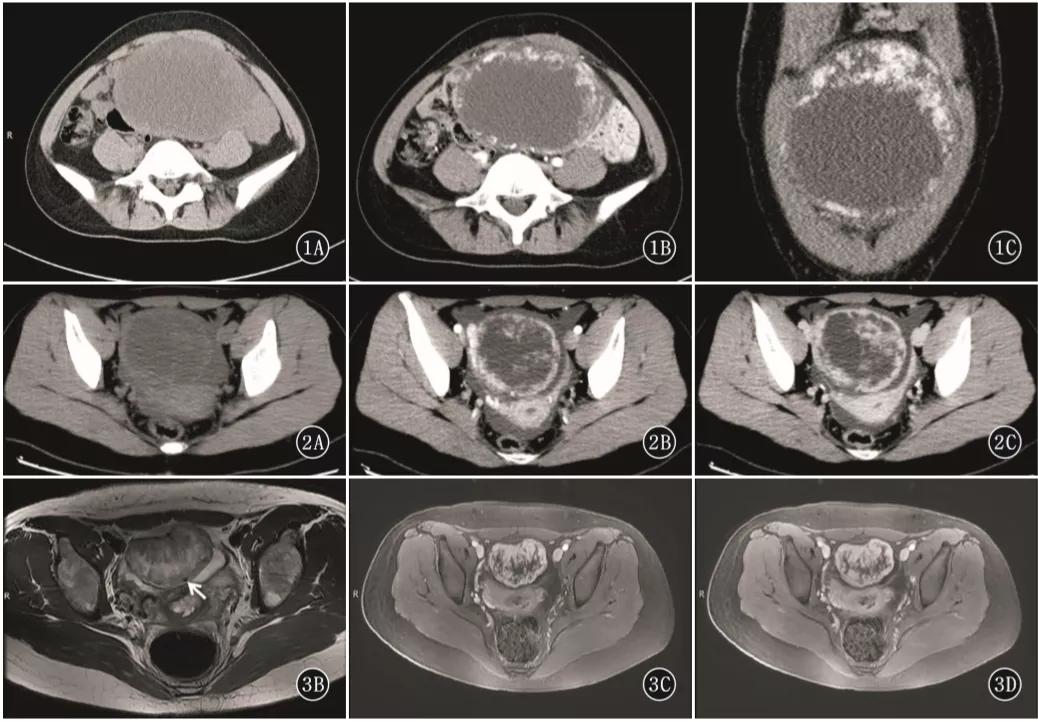

女,18 岁,卵黄囊瘤(右侧),AFP 升高。T2WI 示卵巢实性为主肿物(图 a),内见低信号纤维血管分隔(白箭),实性成分 DWI 呈高信号(图 b),增强扫描明显强化(图 c),内见无强化坏死区(箭头)。

女,50 岁,卵巢类癌与成熟畸胎瘤及卵巢甲状腺肿。左卵巢囊实性肿物,实性成分 T2WI 呈低信号(图 a 黑箭),T1WI 呈稍低信号(图 b),T1WI 压脂呈稍高信号(图 c),DWI 呈高信号(图 d),增强扫描明显强化(图 e)。肿物内囊性成分 T1WI 呈高信号(白箭头)。肿物并存成熟畸胎瘤(白箭)

女,12 岁,卵巢 Burkitt 淋巴瘤。双侧卵巢肿物,T2WI 信号稍高(图 a),DWI 呈高信号(图 b),增强扫描明显强化(图 c),箭头显示肿物边缘多发囊性结节,为卵泡保留征。

女,34 岁,胃癌双侧卵巢转移瘤。T2WI 显示双侧卵巢实性肿瘤,T2WI 呈高低混杂信号(图 a),DWI 呈高信号(图 b)。